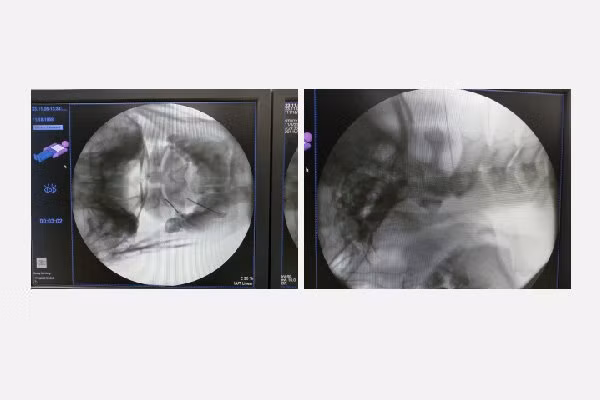

Ca đốt sóng cao tần xung được thực hiện trong vòng 8 phút, với dòng điện kích thích 55 V tạo nhiệt độ 42 độ C. Sóng cao tần xung sẽ làm phá hủy xung dẫn truyền thần kinh ngoại biên chi phối cảm giác của vùng chẩm, giúp người bệnh sẽ mất cảm giác đau ngay sau can thiệp. Người bệnh hồi phục rất nhanh, những cơn đau đầu gần như không còn, người bệnh ăn uống và sinh hoạt bình thường và đã được ra viện sau 1 ngày.

Hình ảnh khi đưa kim đốt sóng cao tần vào đúng vị trí giải phẫuHình ảnh khi đưa kim đốt sóng cao tần vào đúng vị trí giải phẫu